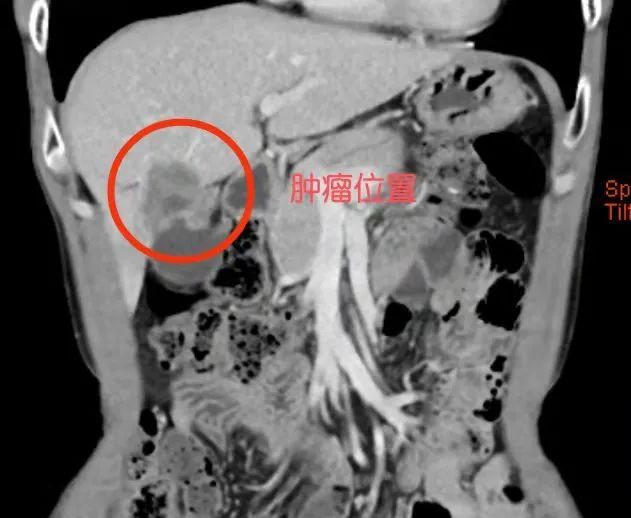

患者术前静脉注射吲哚青绿后术中使用荧光腹腔镜显影出肿瘤的位置和边界

荧光腹腔镜显像导航技术,是向体内注入近红外荧光染料吲哚菁绿(ICG),与血浆白蛋白和球蛋白结合,肝脏正常组织能够排泄而肿瘤排泄障碍的原理,达到肿瘤特异性显像的目的。随后,由肝胆外科医师、麻醉师及护理人员组成的团队凭借熟练的配合和精湛的技术,顺利完成手术。46岁的谭先生也因相似的情况使用了该项技术进行手术,术后在肝胆外科医护人员的精心照顾下,恢复良好。